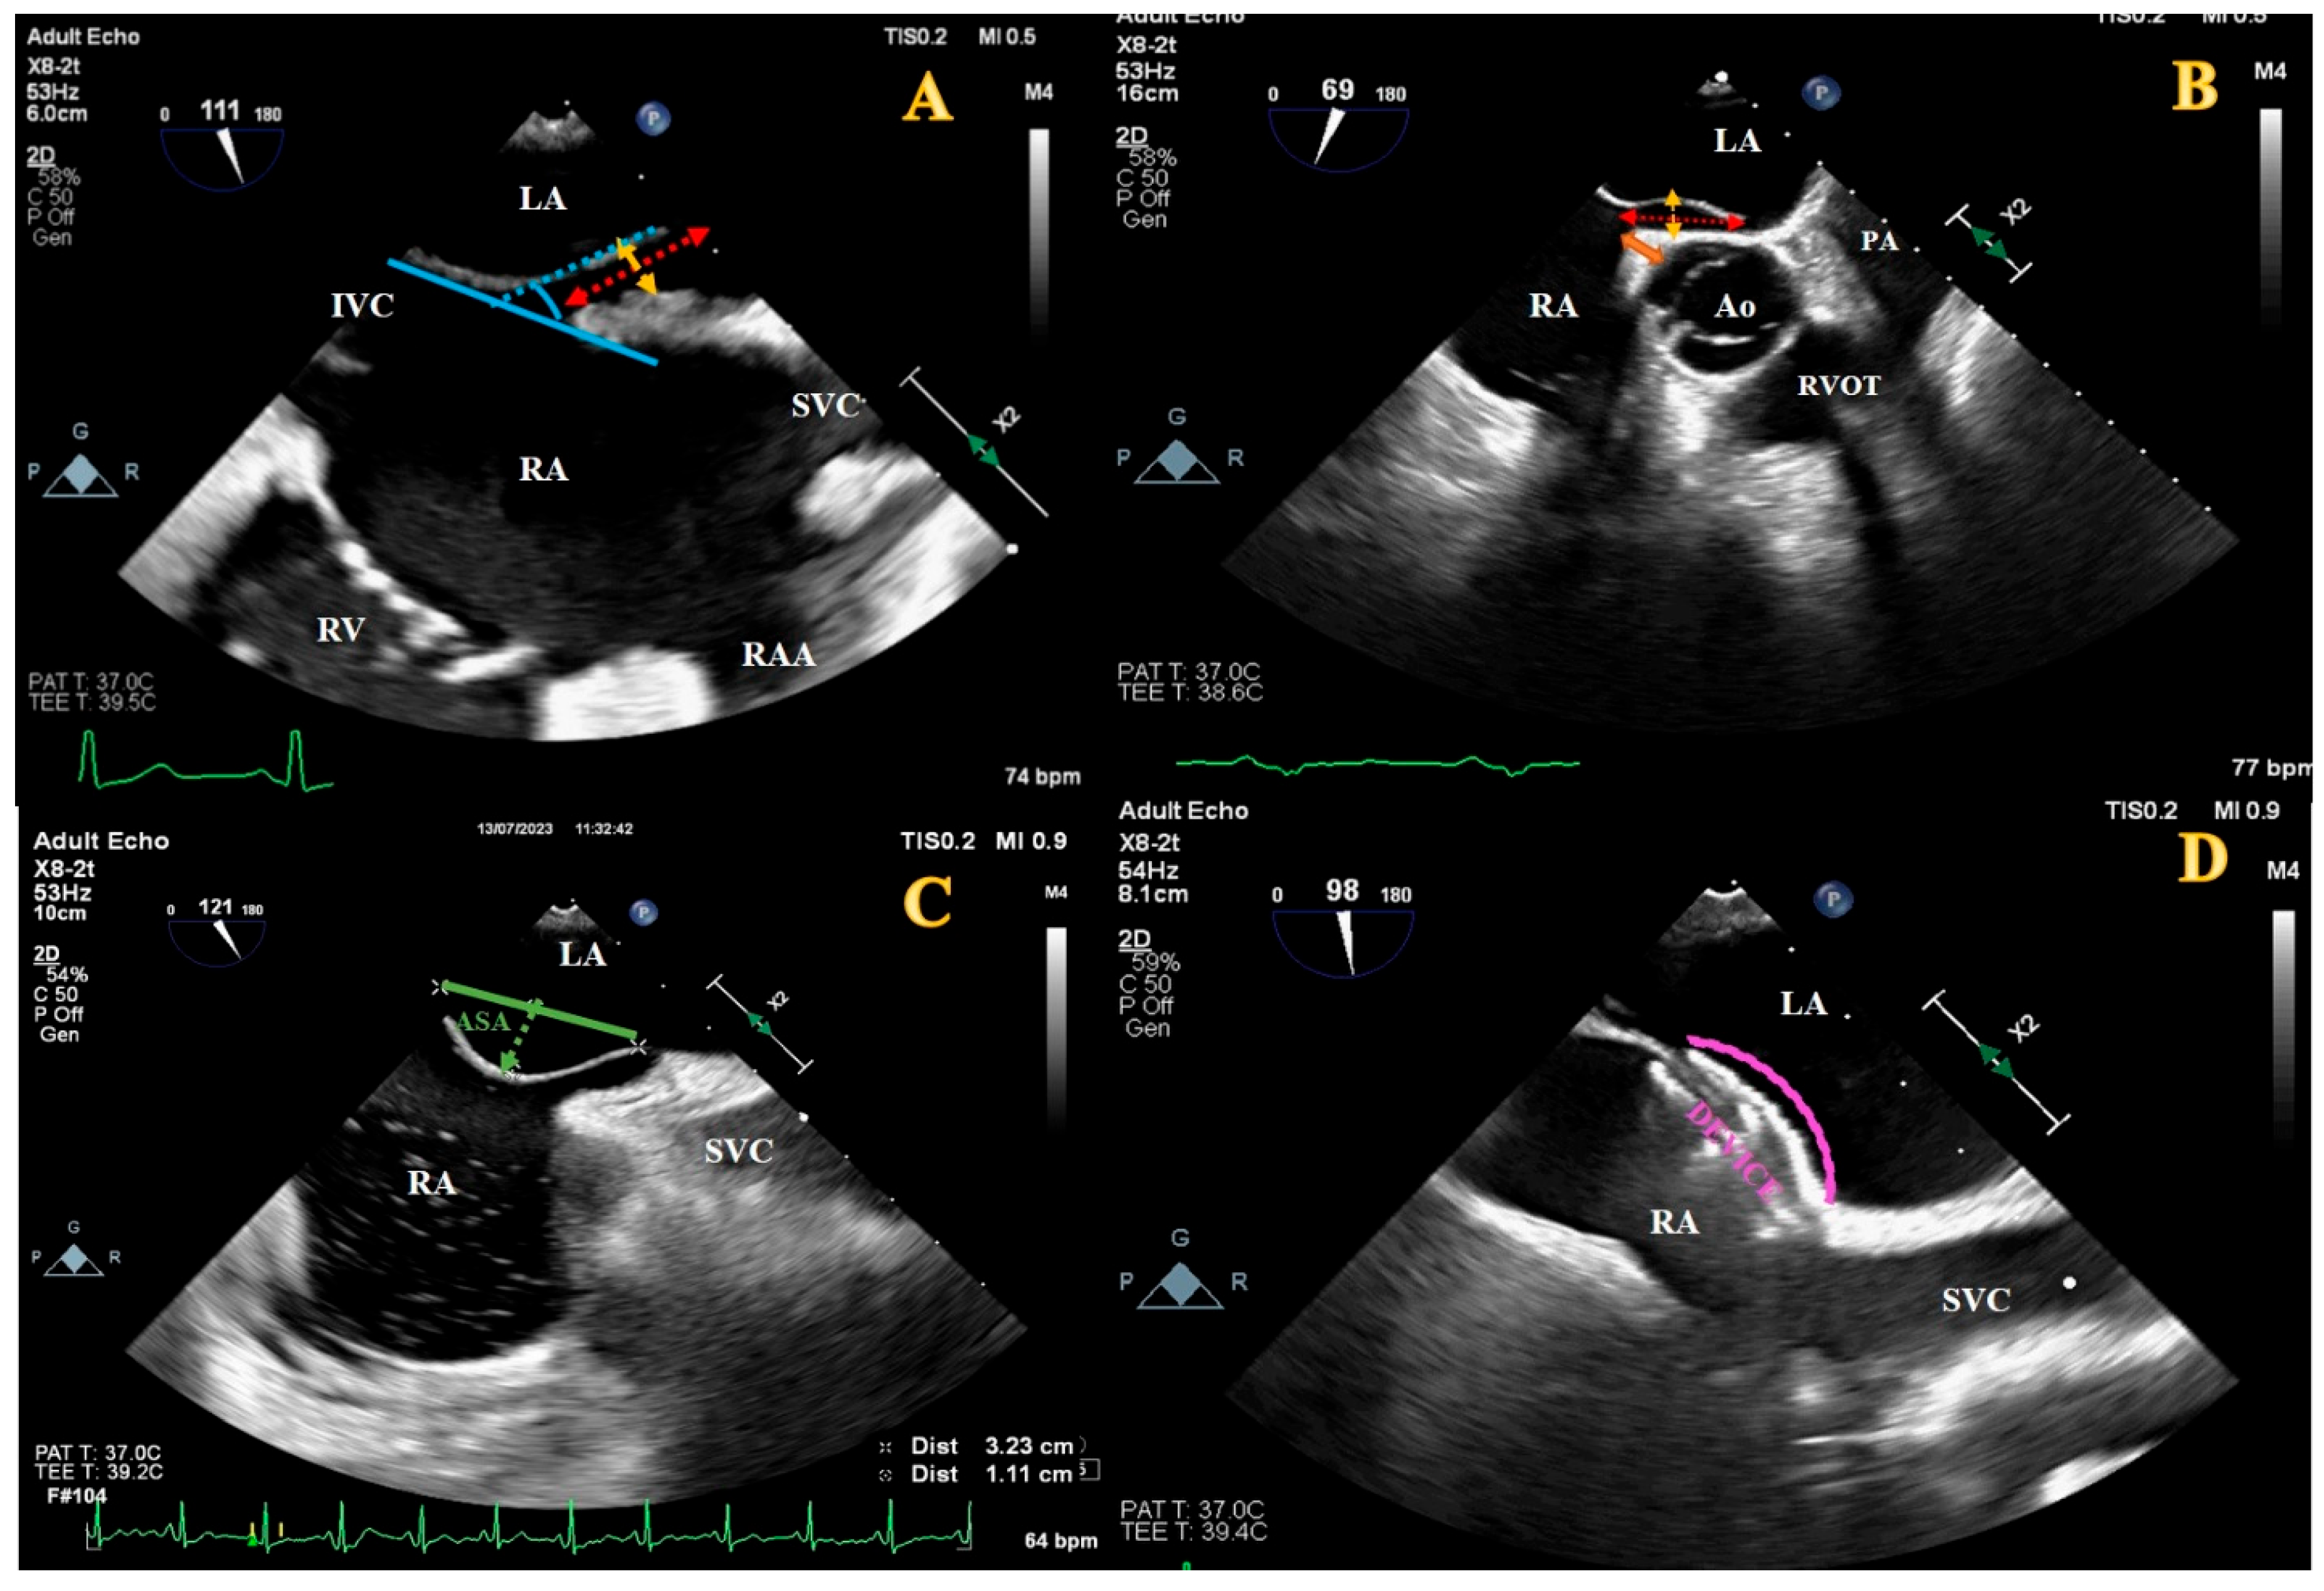

2.2. Definitions and Echocardiographic Evaluation

| VCI-PFO tunnel angle, degree | 21.0 ± 10.6 | 12.5 ± 4.9 | <0.001 |